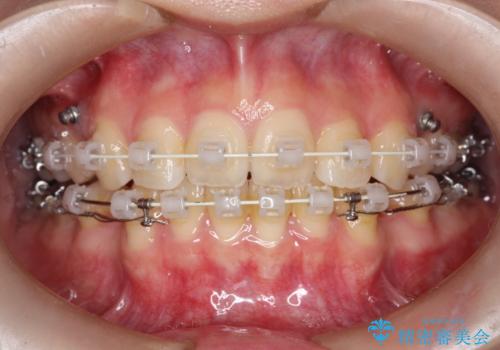

ワイヤーによる抜歯矯正でガタガタの改善

- 前歯のがたがたを主訴に来院されました。

上下の前歯が前方に傾斜しているのもあり、内側に前歯をひっこめるために上下左右の歯を1本ずつ抜歯して矯正することとしました。

ガタガタも改善しましたが、前歯が内側に引っ込むことにより口元もすっきりして、唇が閉じやすくなりました。